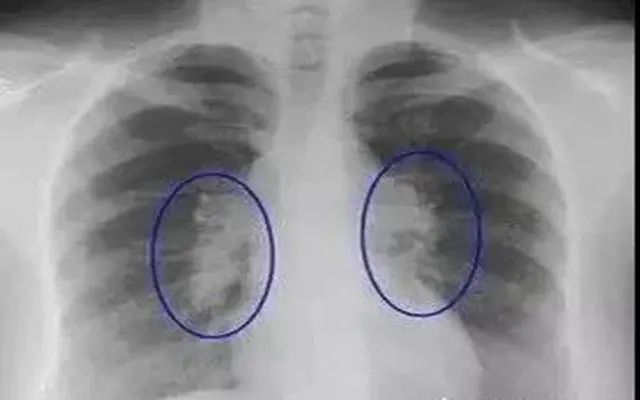

一、结节:大部分都是良性的

在影像检查中(如CT、胸片),小结节或微小结节发现得越来越多,但大部分是良性的。